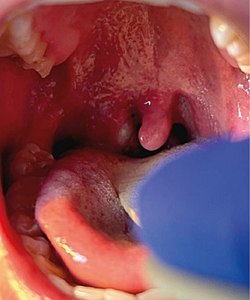

Right tonsillar enlargement with an overlying pustular lesion during the 2022 outbreak.

It is possible for a person to be infected with monkeypox without showing any symptoms.[38] Monkeypox symptoms tend to begin 5 to 21 days after infection,[6] with early symptoms including headache, muscle pains, fever and fatigue, initially resembling influenza.[3][39][40] Within a few days of the fever, lesions characteristically appear on the face before appearing on the trunk then elsewhere such as palms of the hands and soles of the feet.[41][42] The disease can resemble chickenpox, measles and smallpox but is distinguished by the presence of swollen glands[3][39] which may appear behind the ear, below the jaw, in the neck or in the groin, before the onset of the rash.[9] Many cases in the 2022 monkeypox outbreak presented with genital and peri-anal lesions, fever, swollen lymph nodes, and pain when swallowing,[1] with some patients manifesting only single sores from the disease.[43]